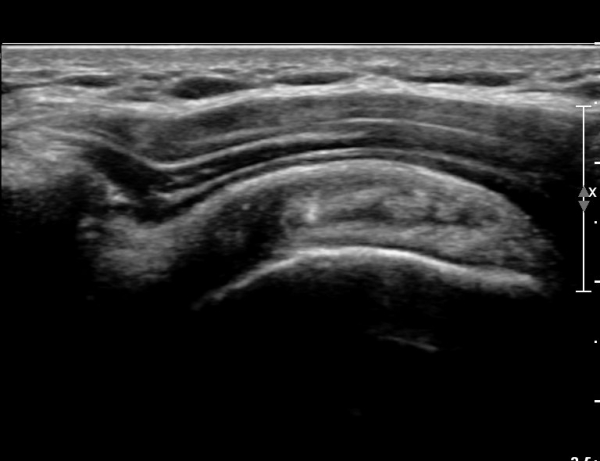

ŽÃËÀÚ¸¦ Á¶±Ý ´õ ¸»´Ü¹æÇâ(caudal)À¸·Î À̵¿ÇÏ´Ï ÆÄ¿­ÀÌ ´õ¿í ¶Ñ·ÈÇÏ´Ù(»çÁø 2, 3).